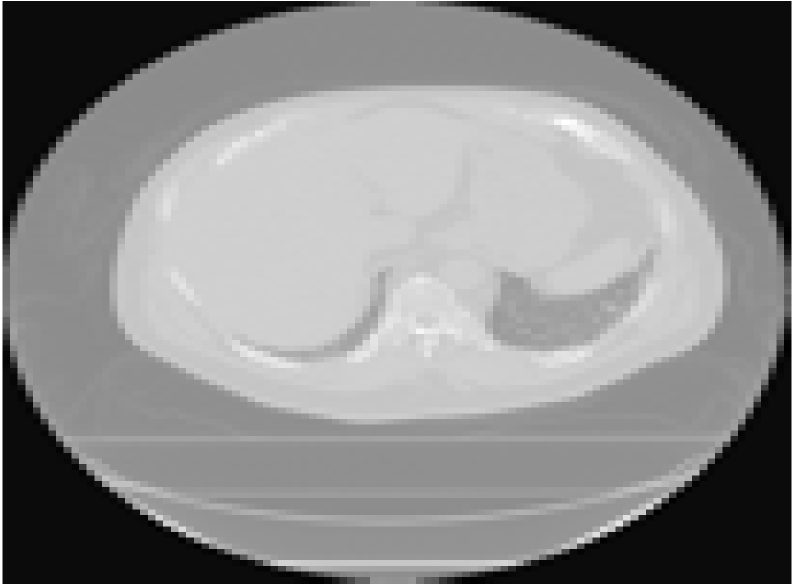

In this section, we consider the application of the methodology to X-ray computed tomography (CT) imaging [49, 50]. First, we evaluate the performance of the proposed methods on real tomographic X-ray data of an emoji phantom measured at the University of Helsinki [51]. The dataset consists of 33-point time series of the X-ray sinogram of an emoji made of small squared ceramic stones. In the sequence, the emoji transforms from a face with closed eyes and a straight mouth to a face with smiling eyes and mouth. Typically, we have a sequence of square X-ray images of size with , which we are interested in reconstructing from low-dose observations taken from a limited number of angles. These low-dose observations can be modeled by the measurement matrix which describes line integrals through the object (i.e., Radon transform).

Fig. 8 shows the CT reconstruction results for the emoji motion dataset, obtained by KS-ADMM. We set the parameters to , , , and . The analysis operator consists of all the vertical and horizontal gradients (one step differences), which corresponds to so called TV regularization [21]. The number of measurements that correspond to or projections are and , respectively. Although there is no ground truth to compare the qualitative results, we can observe the visual results from different numbers of projections. When the number of projections is , the method provides good reconstruction results with iterations. We see that the 30-projection results suffer from the block artifacts as a consequence of the reduction in dose.

Furthermore, we validate the effectiveness of the proposed method on the real inhalation (iBH-CT) and exhalation (eBH-CT) breath-hold CT images, which was acquired as part of the National Heart Lung Blood Institute COPDgene study [52]. The dataset consists of 10 expiratory phase images of the segmented lung voxels. In detail, the parameters are , , , , , and the numbers of measurements are and , corresponding to and projections. The ground truth and the reconstruction results are shown in Fig. 9. By visually comparing the results, we observe that moving from to projection provides much more drastic change. For example, some additional artifacts exist, but the result with the setting and is still very much acceptable (see the third column in Fig. 9). The results show that our methods still successfully preserve temporal information when the number of projections is .

In the two experiments, we used a stationary Kalman filter and smoother to implement the optimization. We pre-computed all the gains before the iteration, which significantly speeded up the computations in tomographic reconstruction. We report CPU time (seconds) in Table IV. Table IV shows that KS-ADMM achieves significantly lower CPU time than the batch ADMM although the visual quality of all the reconstructions is equal. For example, in emoji motion dataset, when , ADMM takes three time longer than our proposed method. In the lung dataset, when and , KS-ADMM seems to be promising to provide computationally efficient reconstruction.